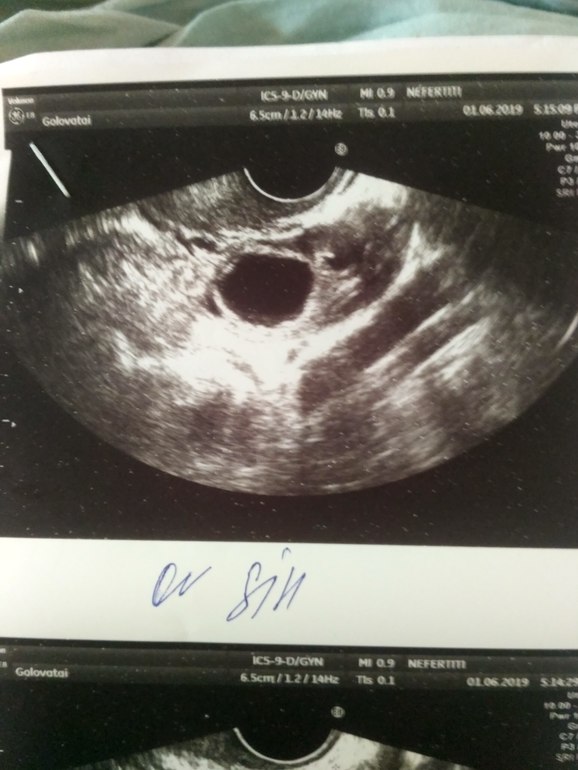

Я конечно не спец, но чето на плодное яйцо похоже. Только вчера на узи была, похожий снимок.

вот такая картина в матке...но она ни чего не сказала,смущает чёрное пятнышко,раньше не было

На фото яичник или матка? Если матка, то это похоже на плодное яйцо, если яичник, то киста желтого тела, которая вполне нормальна при беременности.

Алла

ПЯ тут однозначно есть! При таком мне врач говорила 1,8 мм, прийти через неделю, через неделю было 4,5 мм и сердцебиение (но это опять же реально только с очень хорошим врачем) Врачи все разные. В другом месте при ПЯ 2,5 мм охала и ахала, ну что очень маленький срок и вроде бы что-то есть. Все же в итоге написала беременность малого срока. Просто вы рано пошли на узи. Советую сдать хгч в динамике и от этого уже отталкиваться.

В общем: в яичнике -желтое тело, по размерам вполне хорошее. В матке плодное яйцо-по размерам недели 2 от зачатия. Если бластоцилла смогла внедрится в эндометрий 6,5-значит ее это устроило. Суть не всегда в толщине-главное однородность. А однородность слоя хорошая, т.к. иных включений кроме темного пятнышка я не вижу.

Учитывая наличие ЖТ, тест и включение в матке это беременность малого срока!